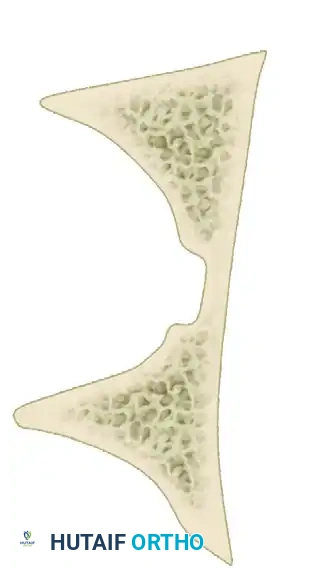

The Letournel and Judet classification system remains the universally accepted framework for categorizing acetabular fractures. It is predicated on the concept of the acetabulum being supported by an inverted "Y" consisting of an anterior column and a posterior column. The system divides fractures into two broad categories: Simple Fracture Types and Associated Fracture Types.

- Transverse Fractures: A single fracture line crosses both the anterior and posterior columns horizontally, dividing the innominate bone into a superior (iliac) segment and an inferior (ischiopubic) segment.

- T-Shaped Fractures: A transverse fracture with an additional vertical fracture line that splits the inferior ischiopubic segment, exiting through the obturator ring.

- Both-Column Fractures: The most complex pattern. All articular segments are detached from the intact posterior ilium (which remains attached to the sacrum).